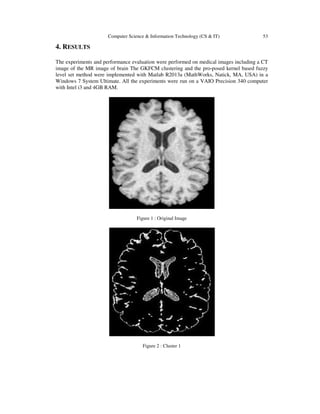

The experiments and performance evaluation were performed on medical images including a CT

image of the MR image of brain The GKFCM clustering and the pro-posed kernel based fuzzy

level set method were implemented with Matlab R2013a (MathWorks, Natick, MA, USA) in a

Windows 7 System Ultimate. All the experiments were run on a VAIO Precision 340 computer

with Intel i3 and 4GB RAM.

Figure 1 : Original Image

Figure 2 : Cluster 1